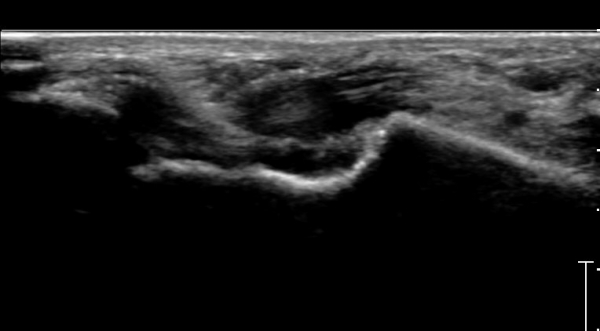

Àü°ÅºñÀδë ÇϺΠÁ¾´Ü¸é°Ë»ç¿¡¼­ Àü°ÅºñÀδëÀÇ Àú¿¡ÄÚ À§Ãø°ú Á·±Ùµ¿ÀÇ ¼ö¾×Àú·ù°¡

°üÂûµÈ´Ù(»çÁø 2, 3, 4).